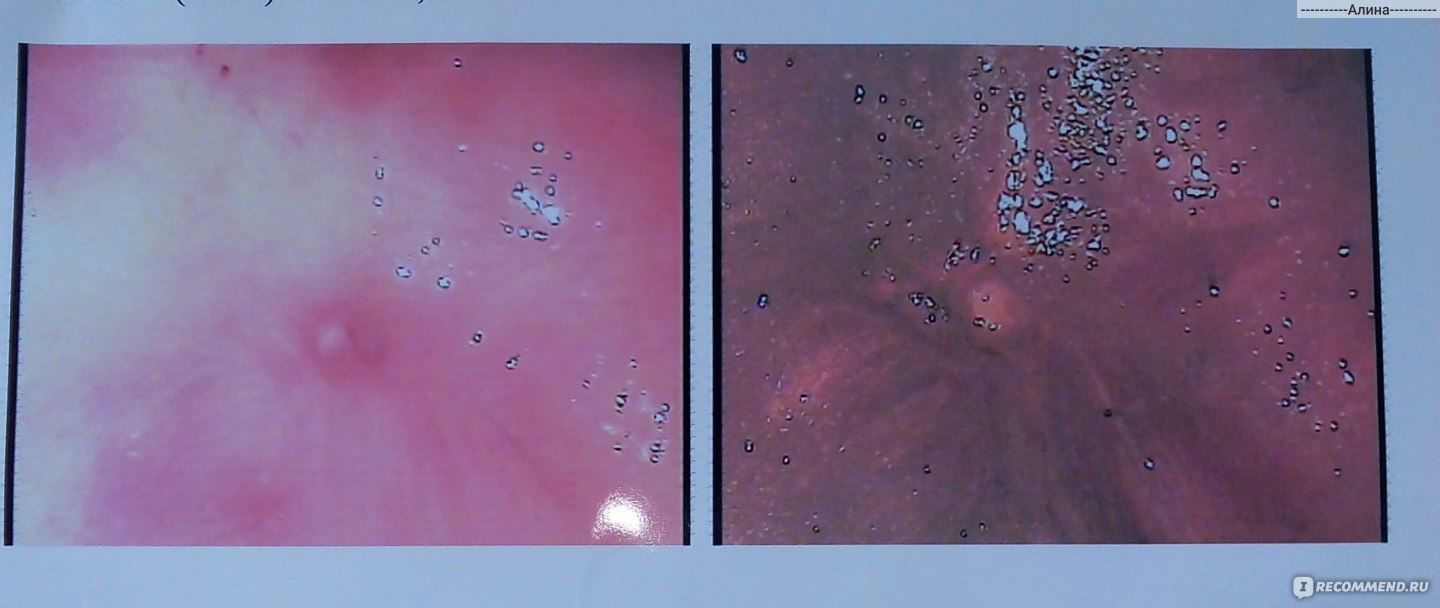

Половые Кондиломы Фото

Половые Кондиломы Фото 116 фото